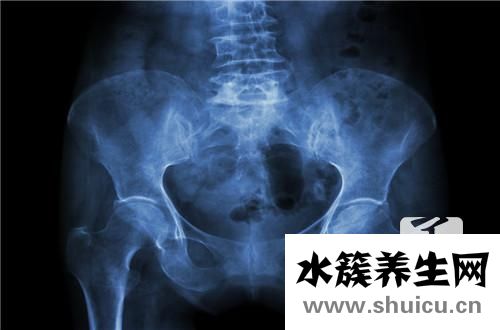

子宮的位置是子宮位于骨盆的位置,可分為頭位、背位和所有正常位置。大多數女性都是子宮前位、子宮前位,這對懷孕是有利的。子宮后位針對女性會有一定的影響,很容易造成白帶過多,小腹痛。另外,非常容易...